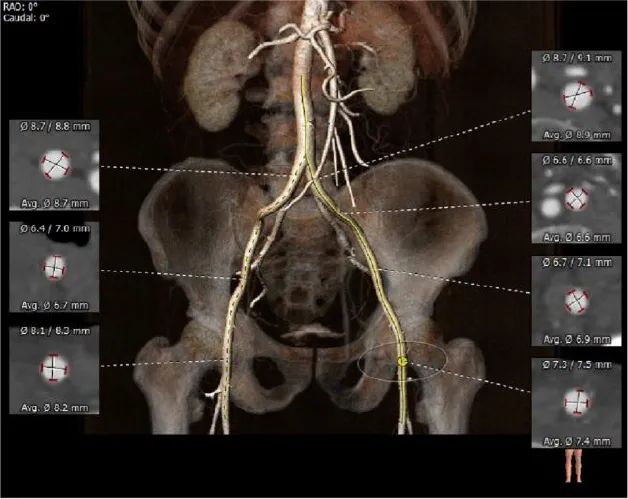

外周血管及主动脉弓解剖:

③入路血管无严重钙化及其他病变,双侧血管内径良好,整体入路血管条件良好。